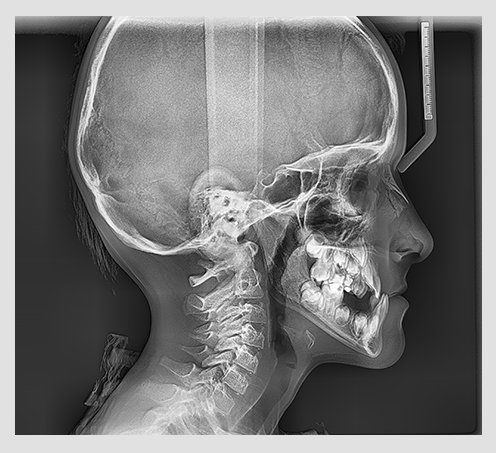

The PaX-i provides optimal images exclusively designed for orthodontics.

There are two image sizes available (lateral and full lateral) that

allow you to choose your image size based on your diagnostic needs.

Provide specialized high-quality images to suit

orthodontics and maxillofacial surgeries.

Full lateral image size is 30% wider and shows the

occipital area of the patient, which enables

comprehensive diagnosis.

| EXAMINATION PROGRAM | SCAN TIME | IMAGE SIZE |

|---|---|---|

| LATERAL | 12.9 sec | 21x23cm (8.3x9.1") |

| FULL LATERAL | 16.9 sec | 27x23cm (10.6x9.1") |